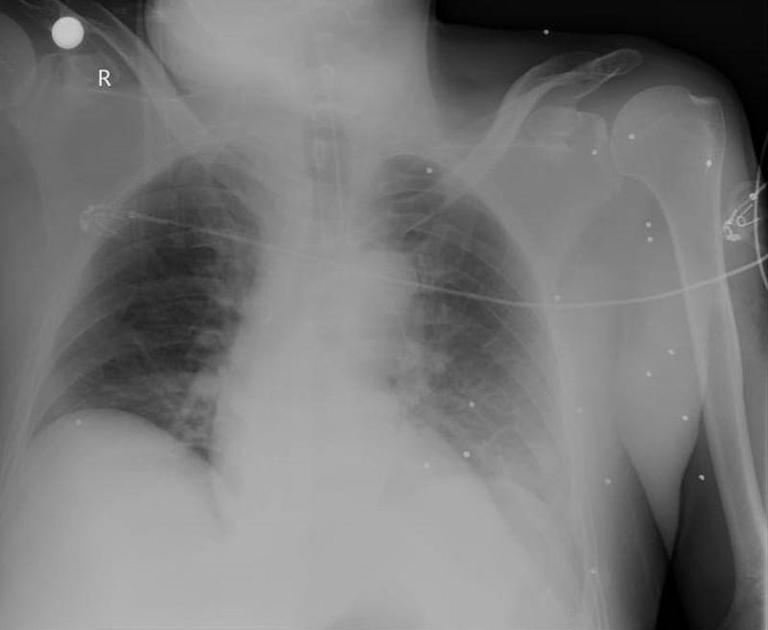

Osman Yıldırım'ın hastanede tedavisi sürüyor. Şu ana kadar 4 ameliyat geçiren Yıldırım'ın vücudunda 3 koldan ve 1 karın bölgesinden olmak üzere toplamda 300 saçma bulunduğu belirtildi. Bu saçmaların 30'u riskli bölgelerde yer aldı.